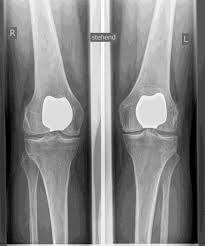

يشار إلى مفاصل الركبة الاصطناعية بالأطراف الاصطناعية الكاملة والأطراف الاصطناعية الجزئية. أتحقق بعناية مسبقًا من الطرف الاصطناعي المناسب لك بناءً على الفحص السريري، وكذلك على أساس صور الأشعة السينية أو التصوير بالرنين المغناطيسي.

يحل مفصل الركبة الاصطناعي محل سطح الغضروف الذي دمره التهاب المفاصل العظمي. يظل العظم الأساسي في عظم الفخذ والرأس الظنبوبي سليمًا. يقارن البعض مفصل الركبة الاصطناعي الحديث بتتويج الأسنان؛ والمصطلح الدقيق هو ما يسمى بإعادة تسطيح اللقمتين. بين الأسطح الجديدة في الجزء العلوي والسفلي من الساق يوجد ما يسمى بالبطانة المصنوعة من البلاستيك الأبيض المقوى خصيصًا، والتي يمكن رؤيتها في صورة الأشعة السينية على أنها المسافة بين الأجزاء المعدنية.